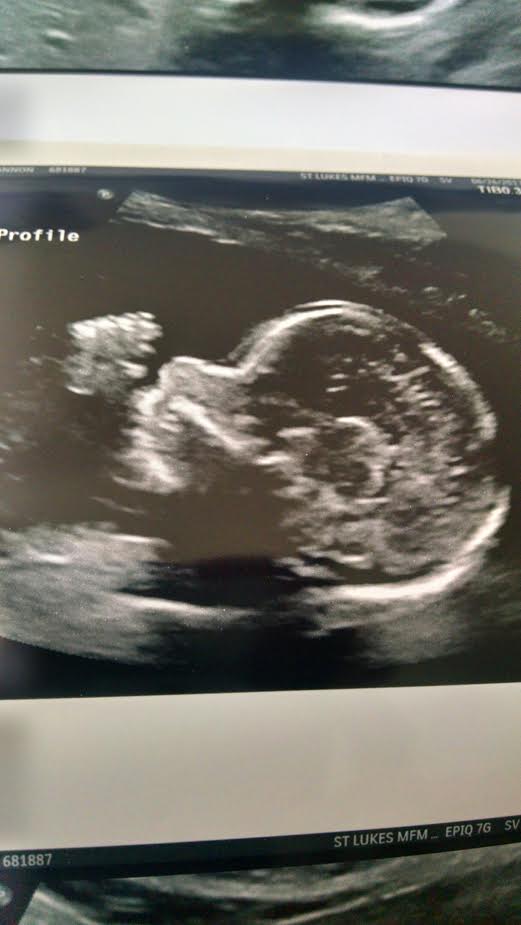

So I would like to see that everyone thinks of these pics from the skull theory. I was 20w exactly.